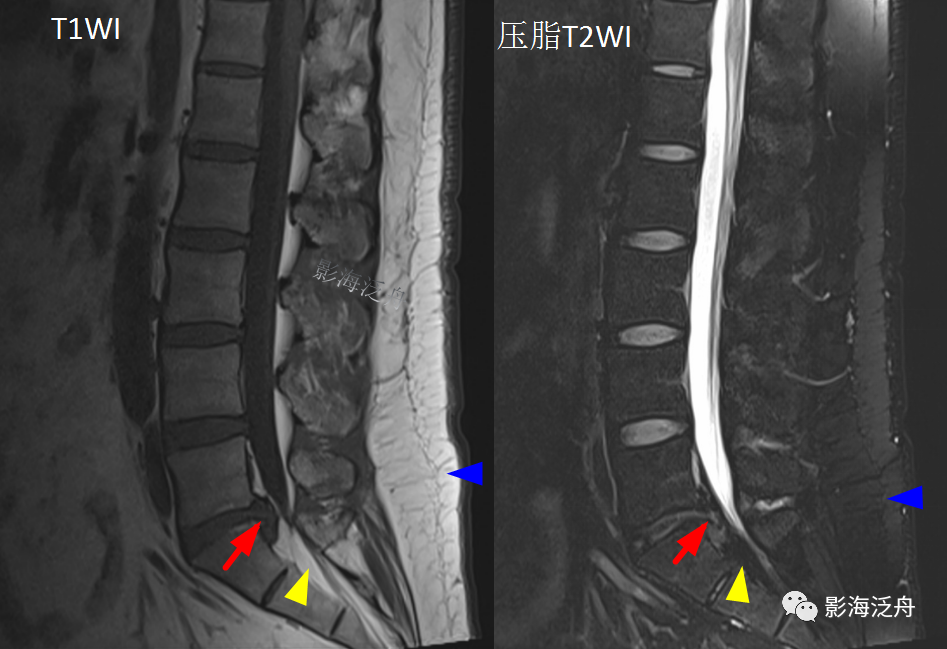

患者二:患者男31岁,也是搬重物后腰部疼痛。可见L5/S1椎间盘呈脱出改变(红箭),但仔细观察可以发现骶椎管内脂肪组织增多(黄箭头),在压脂T2WI序列呈低信号,与腰背部的皮下脂肪信号改变一致(蓝箭)。

病例二患者的L5/S1水平横断位像,可见椎管内硬膜囊外脂肪增多(黄箭头),硬膜囊受压,硬膜囊内的马尾神经呈聚拢改变(绿箭)。

最后,把正常和异常图像放一起再次对比观察,加深记忆!

(注:上面两幅图都是T1WI,由于是不同厂家仪器扫描,所以图像质感有差异)